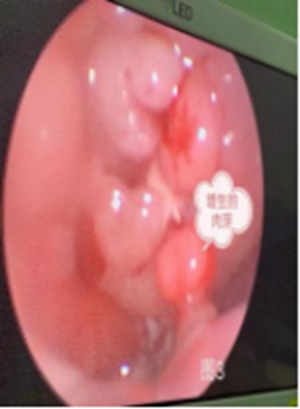

因“藏”的時間太久,導(dǎo)致:

螺絲釘已經(jīng)與鼻腔黏膜粘連的非常嚴(yán)重;

周圍的黏膜組織已出現(xiàn)部分壞死;

加上長時間的異物刺激,小帥鼻中隔的后緣已經(jīng)出現(xiàn)了肉芽增生。